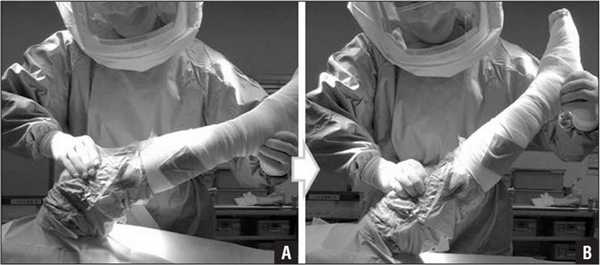

Эластичное бинтование

На протяжении 6 недель после выполненной операции есть риск тромбов и отечности. Поэтому специалистом в раннем периоде назначается эластичное бинтование, в более позднем - компрессионные чулки. Степень компрессии данных медицинских изделий подбирает ортопед, учитывая объемы вмешательства и фактор предрасположенности к тромбообразованию. Наложение эластичного бинта и ношение компрессионного белья препятствуют развитию тромбоза глубоких вен.

Бинты используются все реже, они очень плохо держаться при движении. Чаще применяют такой компрессионный трикотаж.

Технике, как бинтовать ногу, вас обучат в стационаре. Сначала бинтование осуществляет врач, а по возвращении домой вам придется это делать самостоятельно. Будьте внимательны ко всему, что говорит и чему учит вас медицинский персонал, пока вы еще находитесь в клинике или реабилитационном центре.